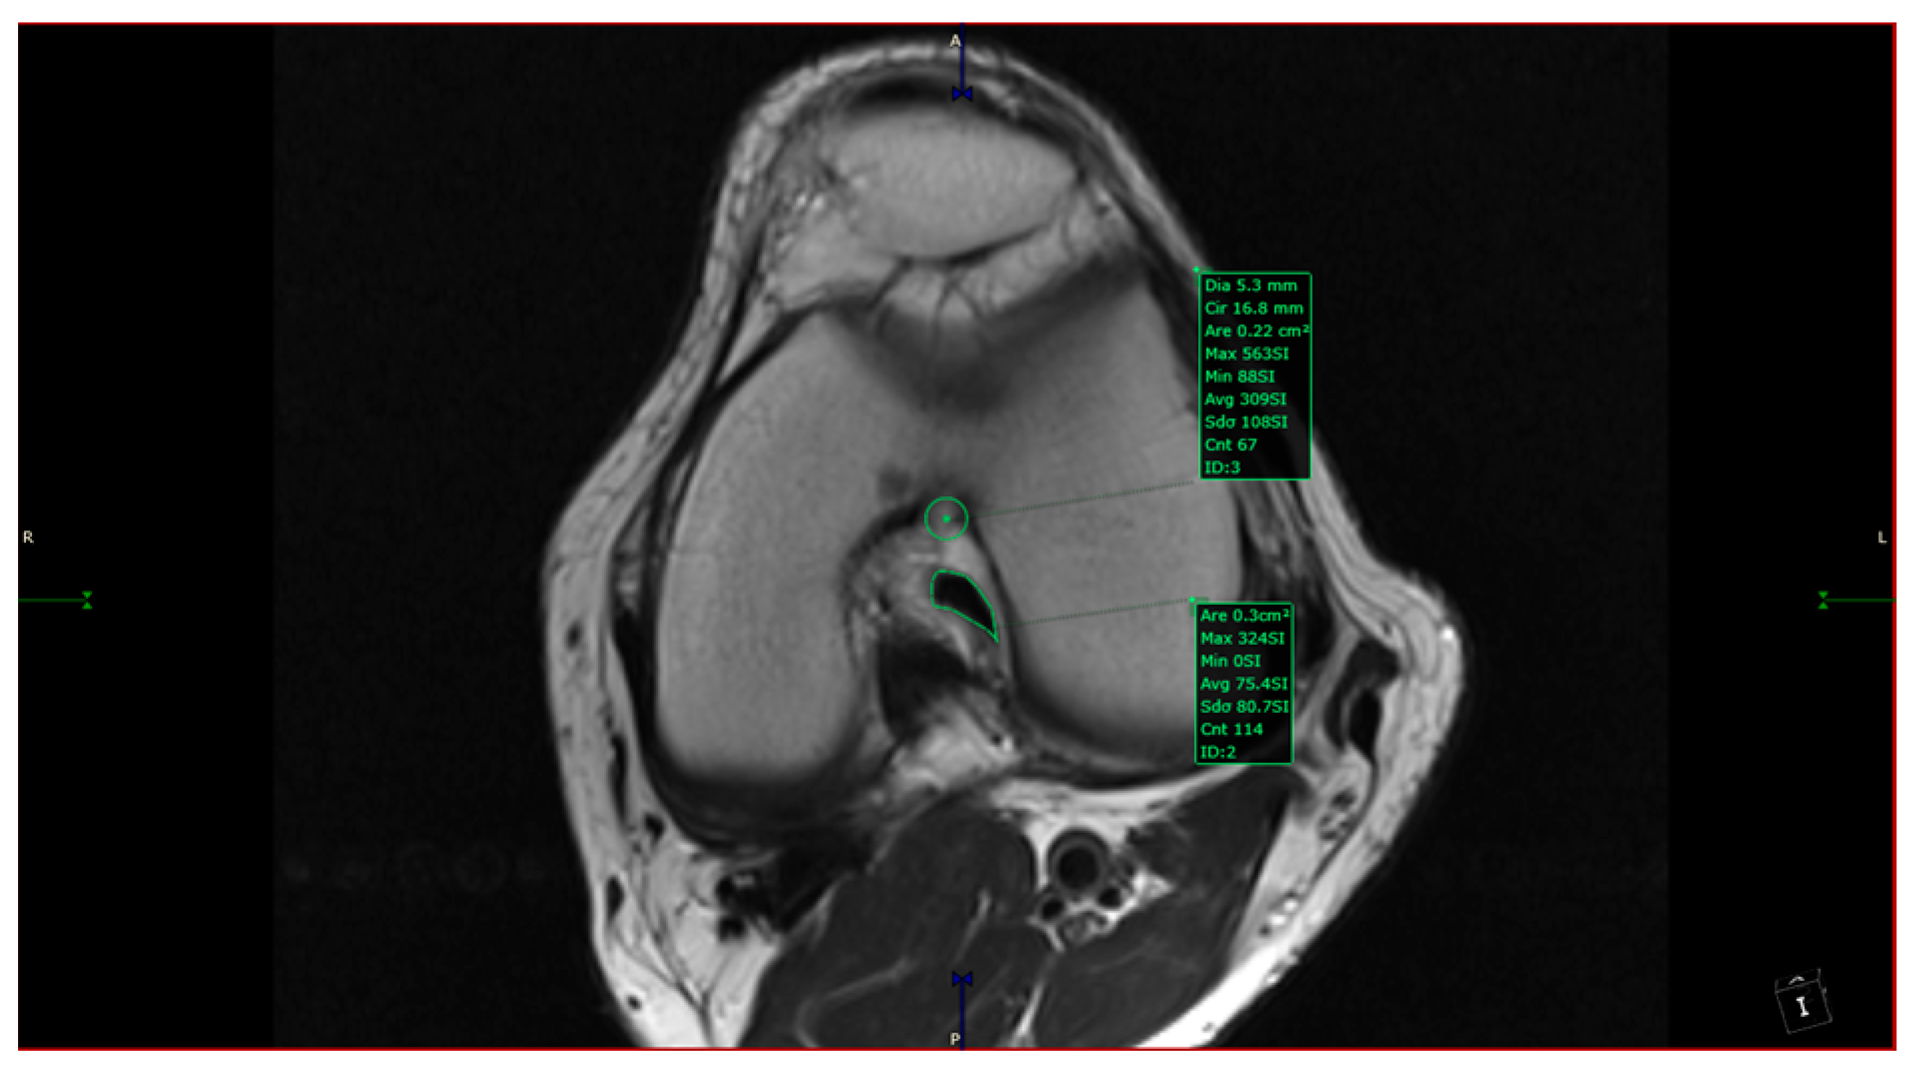

- ACL area: area of the closed polygon defined by pointed dots around the cross-section of the anterior cruciate ligament (in the CAP; Figure 4).

- aICN area and ACL area (both appear in Figure 6).